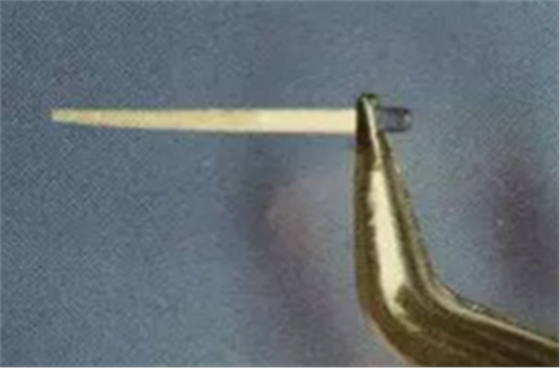

(剪去吸潮紙尖尖部)

(圓形根管的干燥)

(扁圓形根管的干燥)

操作時(shí):剪去紙尖尖部,插入根管,稍微加以壓力,上下小幅度貼根管壁四周提拉,均勻吸收水分。當(dāng)扁圓形根管時(shí)可使用兩根大錐度牙膠尖。